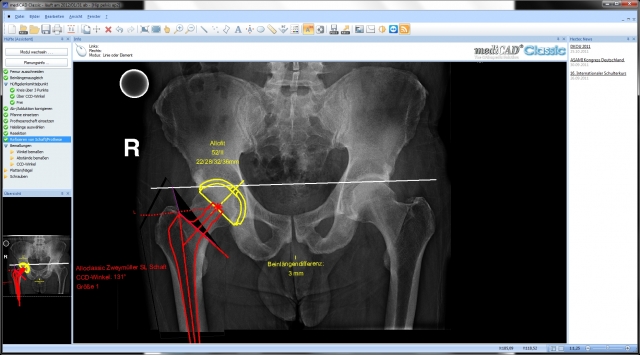

Version 2.50 integrates more than 100 new features and requests from people who use the software on a daily basis. Experiences of clinics and practices from around the world were taken into consideration. According to Jörn Seel, Managing Director of hectec GmbH: "Every new function and change focused on one key goal: maximizing certainty for the surgeon." As a secondary objective, the program interface was modernized and operating procedures revised. For example, the surgeon can now choose to plan a hip automatically or step-by-step manually. Leg length compensation and refixation can also be handled automatically or step-by-step in Expert mode.

mediCAD Classic covers all areas of orthopedic surgery, from hips to the shoulders and feet and from the knees to the spinal column, documenting all procedures in a legally secure way. The mediCAD database currently includes products from 90 global manufacturers and covers more than 80% of all implants used in Europe.